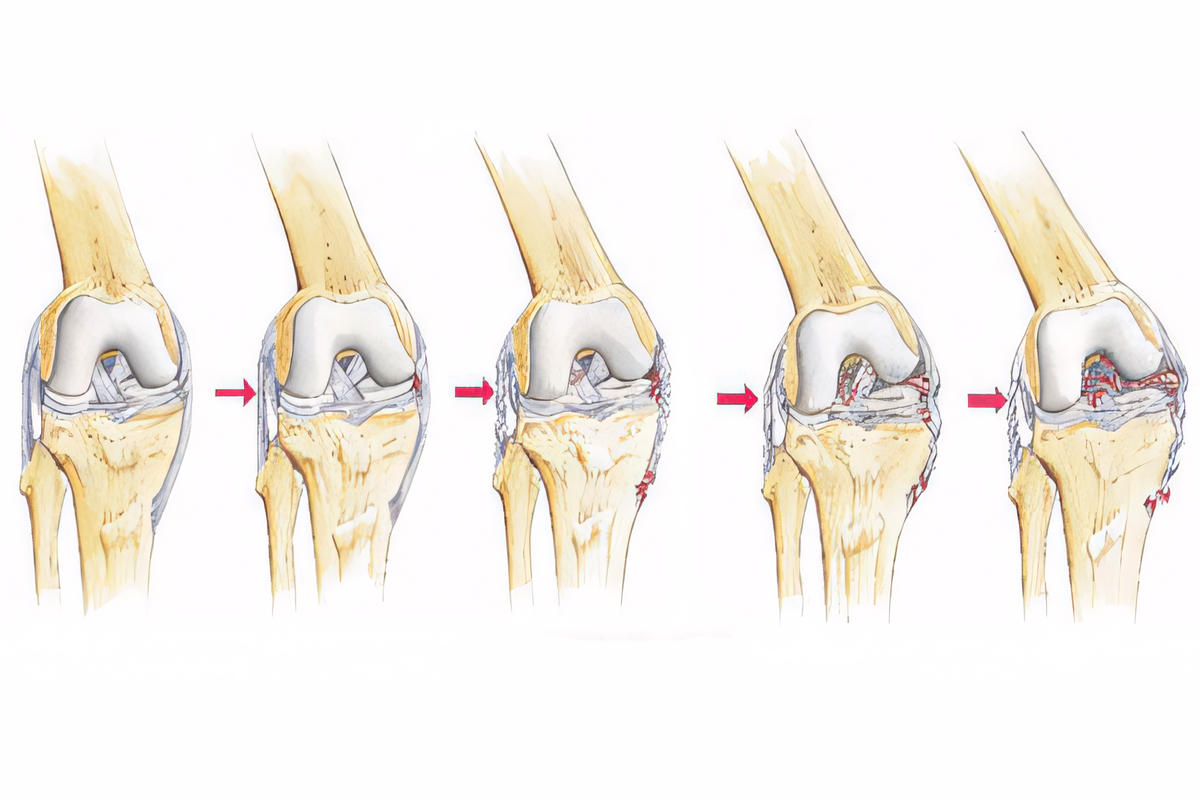

Η ρήξη διακρίνεται σε τρεις βαθμούς:

Ρήξη 1ου βαθμού

Ήπια διάταση ή μικρή ρήξη ινών χωρίς ουσιαστική αστάθεια.

Ρήξη 2ου βαθμού

Μερική ρήξη με εμφανές οίδημα, πόνο και μέτρια αστάθεια.

Ρήξη 3ου βαθμού

Πλήρης ρήξη με σημαντική αστάθεια και δυσκολία στήριξης.